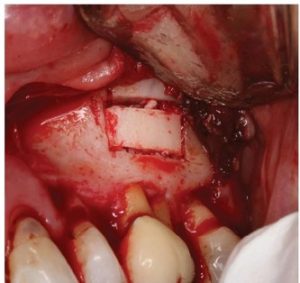

The cortical window was placed in sterile saline while the endodontic microsurgery was completed. After resection

using Lindemann burs, the root periphery was stained with methylene blue and examined for anomalies and the root canal space was retro-prepared with ultrasonic tips to a depth of three millimetres, creating a reservoir for the retro sealing materials.

The retro-preparation was rinsed with ethylenediaminetetraacetic acid (EDTA) and dried with paper points.

Bosworth Super-EBA was placed (Figure 11) and the root end burnished with a multi-fluted carbide bur. Radiographs were taken at the retro-preparation stage and the retro sealing stage to ensure accuracy of direction and material placement. The defect thoroughly debrided and was grafted with allograft (Straumonn Allograft) (Figure l 2). The cortical bone window was replaced and ensured to have no mobility (Figure 13)